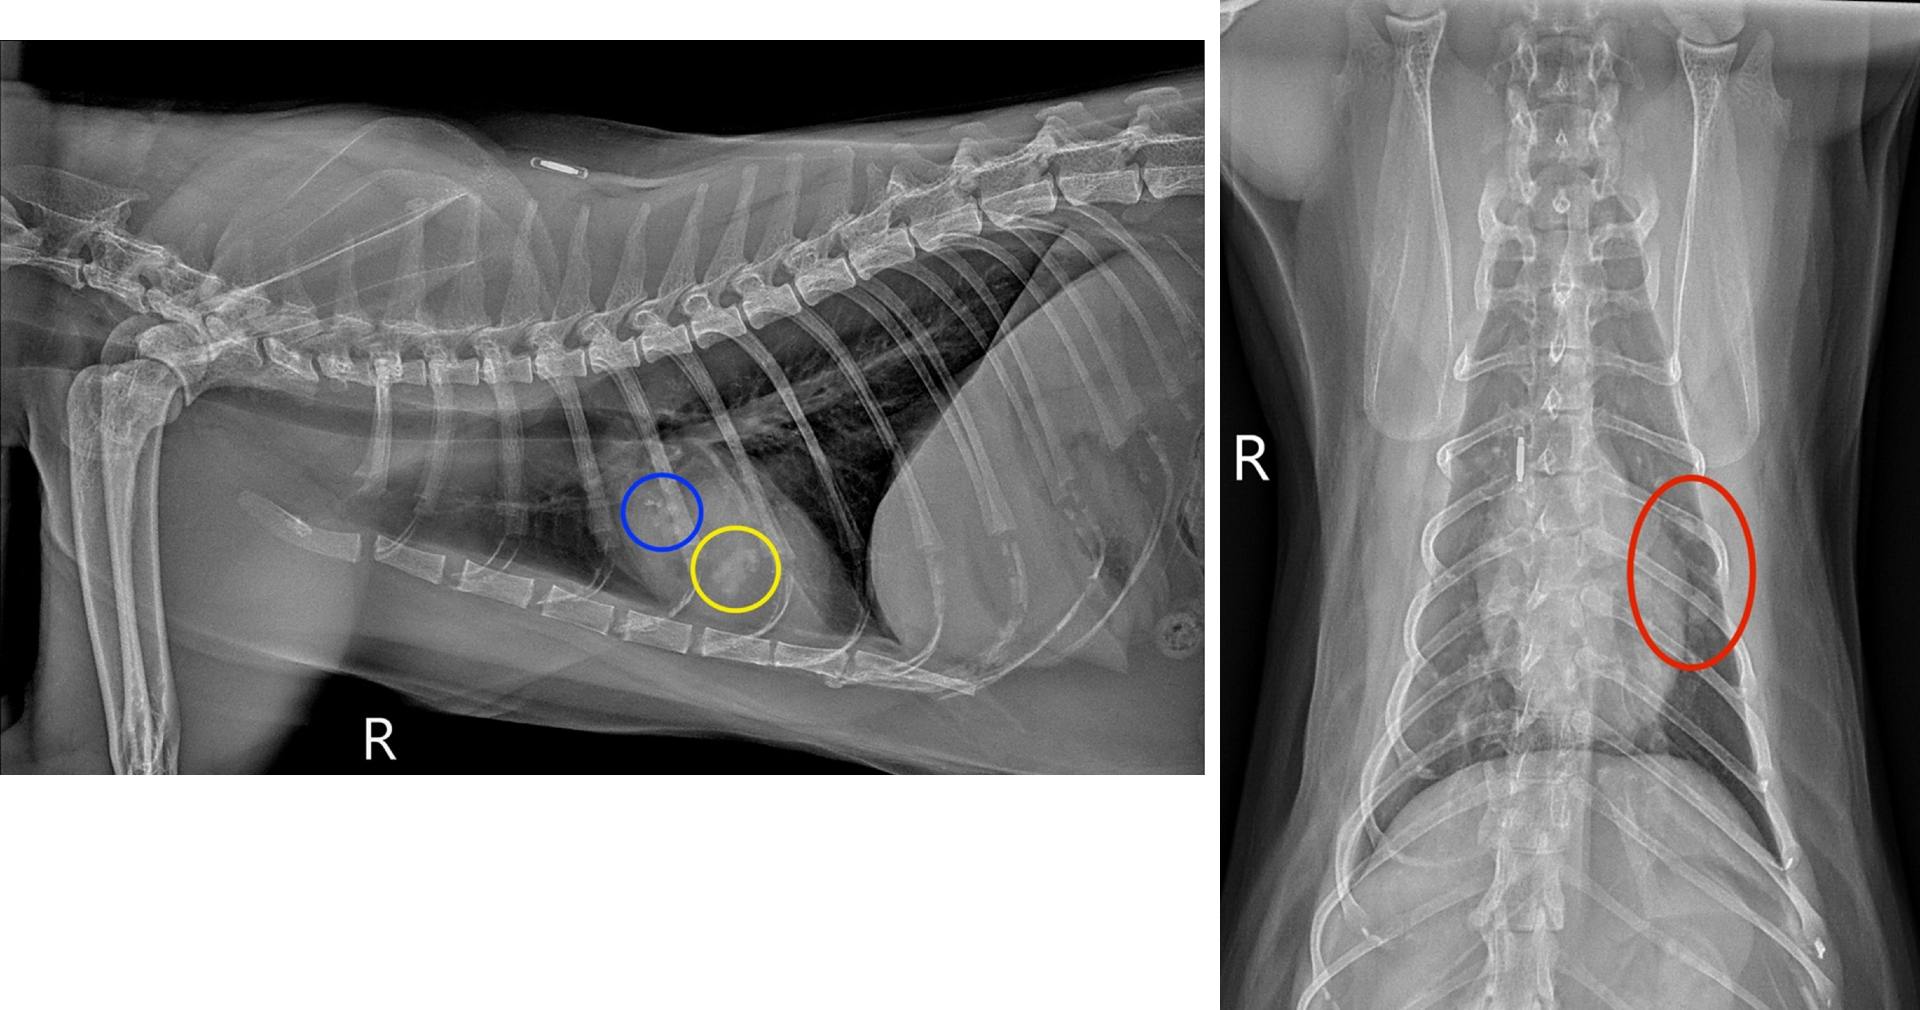

A multilobulated, mixed soft tissue and mineral opaque lesion (circled in blue) measuring 1.0 x 0.5cm is in the plane of the left cranial lung lobe on the right lateral view, partially superimposed over the 5th ribs and the heart. A second multilobulated, but primarily soft tissue opaque lesion (circled in yellow) measuring 0.6 x 0.9cm is also identified on the right lateral view, located in the 5th intercostal space caudoventral to the first described lesion. Both lesions have a linear branching and nodular appearance that creates a “tree-in-bud” pattern. On the ventrodorsal view, both lesions are in the region of the left cranial lung lobe (circled in red), which is in a similar location as the pulmonary focus seen on prior thoracic radiographs. A mild diffuse bronchial pattern was also noted.

Based on the appearance of the left cranial lung lobe lesions and concurrent mild bronchial pattern, lower airway disease (feline asthma vs chronic bronchitis), bronchial plugging, and broncholithiasis/peribronchial gland mineralization were strongly prioritized over other differentials, such as neoplasia. To further evaluate these findings a sedated, non-contrast thoracic CT was performed immediately following the radiographs.